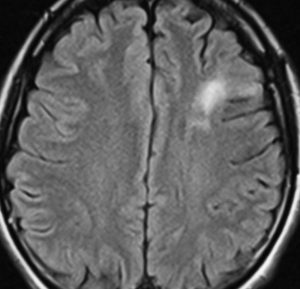

フレア画像です。左上前頭回の星細胞腫ですが,境界がとてもはっきりしていて限局性 localized single gyrus glioma です。びまん性 diffuseには見えません。IDH1の変異があり,1p/19qの欠失はないので星細胞腫グレード2です。上の例とは全く違う臨床像を示しますが,分子病理でも区別はつきません。頑張って早めに全摘出して治してしまった方がいいタイプです。再発を避けるために,supratotal resectionと言って,周囲の正常脳組織も10mmくらい余分に摘出します。